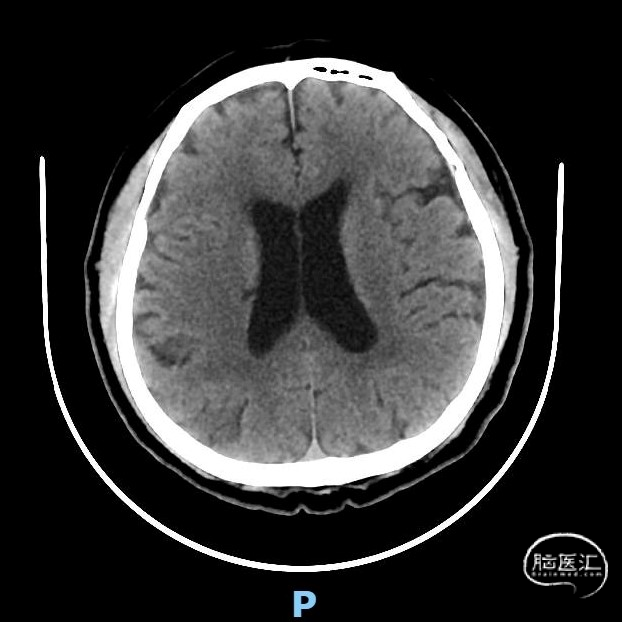

术前颅脑CT示:右侧脑室旁陈旧性腔梗。

术前头颈部CTA示:(1)左侧锁骨下动脉、左颈总动脉、右锁骨下动脉起始部、双侧颈内动脉粥样硬化表现。(2)右侧椎动脉起始部粥样硬化表现,管腔中-重度狭窄。